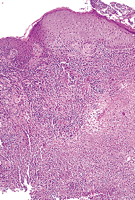

On examination, the patient was afebrile. A 2.5-cm-diameter nodule with a 1-cm deep ulceration was located on the dorsum of the left wrist. A curvilinear erythematous patch extended from the nodule radially and proximally (Figure 1). At the time of presentation, 2 firm subcutaneous nodules without overlying skin changes were palpable over the left biceps. Three biopsy specimens from the periphery of the nodule were obtained for culture and pathologic examination (Figure 2, Figure 3 and Figure 4).

The biopsy specimens showed an area of central dermal necrosis surrounded by a mixed infiltrate of lymphocytes, histiocytes, plasma cells, and neutrophils. Occasional multinucleate giant cells were present. A Gomori methenamine-silver stain revealed yeast forms, some of which had a round or an elongated bud (Figure 4). The fungal culture yielded Sporothrix schenkii in a characteristic dark, leatherlike plaque (Figure 5).